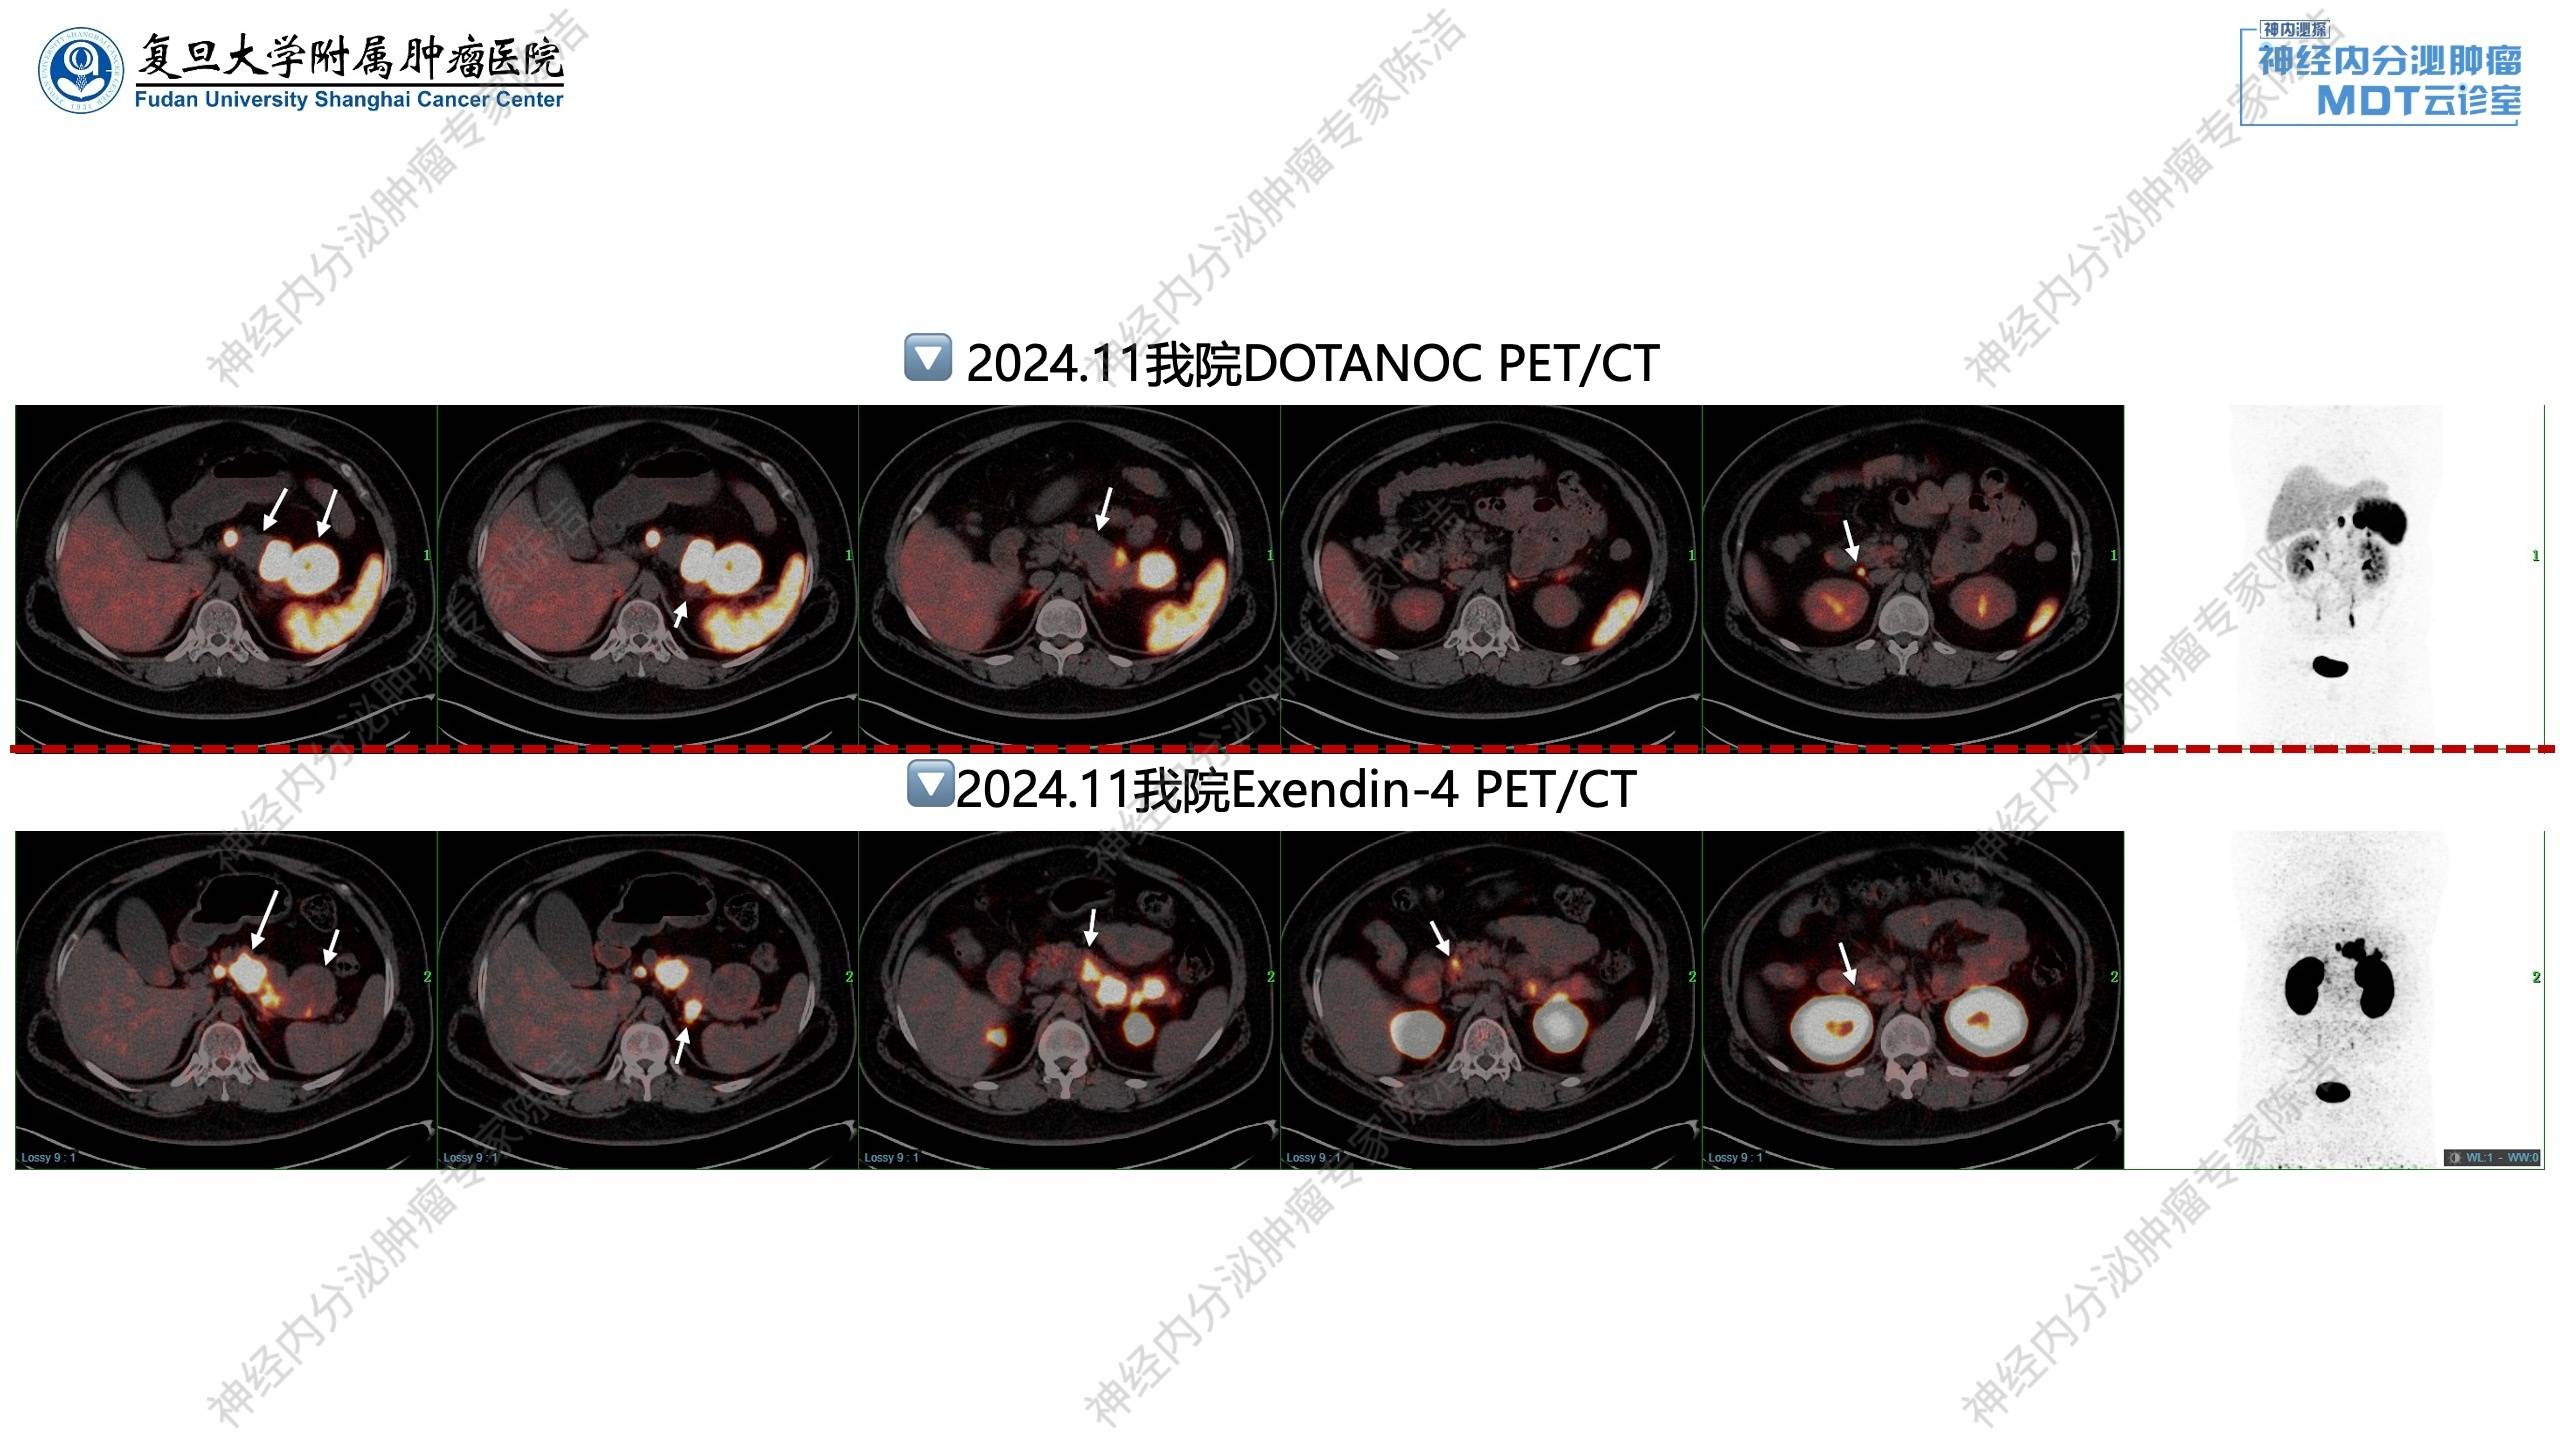

68Ga-DOTANOC-PET/CT示:胰腺及十二指肠降部多发NET,肠系膜根部及胰头后方多发淋巴结转移,生长抑素受体高表达,SSTR-RADS 5;垂体饱满,NOC摄取轻度增高,生理性摄取与pitNET难以鉴别。

患者虽无典型低血糖临床表现,但实验室检查发现血葡萄糖明显下降,予进一步完善GLP-1R-PET/CT,结果示:与2024年10月11日NOC PET/CT相比较,胰腺全程多发NET,部分SSTR高表达,部分GLP-1R高表达,GLP-1R高表达者考虑为胰岛素瘤,主要定位于颈体尾,胰头部仅见钩突一枚小病灶;胰尾后方淋巴结转移,GLP-1R高表达,SSTR不表达;肠系膜根部及胰头后方转移淋巴结,十二指肠降部病灶,SSTR高表达,GLP-1R不表达。

核医学科徐俊彦教授:该患者实验室检查发现低血糖,通过GLP-1R-PET/CT发现胰颈后方大病灶和胰头钩突部微小病灶均呈GLP-1受体高表达。这帮助外科医生精准定位了分泌胰岛素的功能性病灶,进行了胰体尾切除和胰头微小病灶的定点剜除,去除了功能性肿瘤,极大提高了患者生活质量。